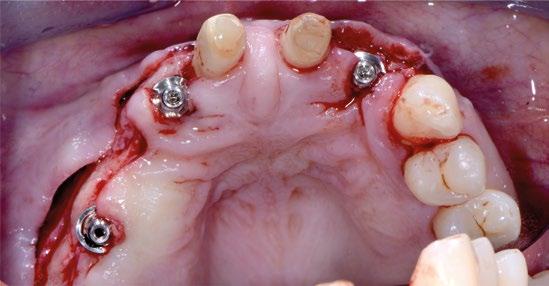

Se planifica tratamiento periodontal para estabilizar la situación de partida, (se recomienda tratamiento de ortodoncia que el paciente declina) exodoncia del diente 2.1, legrado minucioso del proceso periodontal asociado, colocación de dos implantes Prama Long neck de manera simultánea a la exodoncia, regeneración ósea guiada de ambos defectos mediante abordaje en tunel, compensación de la pérdida de volumen mediante la colocación de tejido conec?vo de paladar a través del mismo acceso y consecución de estética inmediata por medio de provisionales atornillados que guíen la cicatrización en forma y posición.

Con la mejora de la situación periodontal tras el tratamiento y la adquisición por parte del paciente de nuevos y mejores hábitos de higiene se procede a la cirugía del sector anterior, motivo por el cual el paciente acudió a la consulta y que condicionaba su vida social.

Se comienza con la exodoncia del 2.1 de forma atraumática y el legrado minucioso del alveolo. Para asegurar la correcta remoción de restos epiteliales de la bolsa periodontal se realiza curetaje rotatorio a baja velocidad con fresa de diamante de grano grueso (aro verde). (Figuras 4 y 5). Para llevar a cabo la regeneración ósea guiada se facilita el acceso tunelizado, mediante dos incisiones VISTA modificadas a nivel de la mucosa alveolar de 13 y 23, de las membranas reabsorbibles así como del injerto de tejido conectivo. A nivel de 1.1 se hace una incisión circular sin descargas a modo de ojal supracrestal.

Una vez desbridados los tejidos cicatriciales y de granulación de ambos defectos y habiendo minimizado la tensión de todo el tejido mucoso diseccionando a espesor total y parcial el túnel se procede a colocar ambos implantes en la posición 3D ideal teniendo como referencia la futura posición de los márgenes gingivales de 1.1 y 2.1. Así, la plataforma de ambos Prama se colocan a 1,5 mm apica -

Apical a esta plataforma queda un cuello tratado específicamente (UTM) para su convivencia con el conectivo supracrestal mejorando la estabilidad de dichas futuras fibras gracias a la convergencia a coronal de los 3 mm de cuello y que en los primeros estadios de cicatrización aportan espacio para el biomarterial y el injerto de tejido conectivo sin que existan presiones nocivas (Figuras 6 y 7).

17

Gracias a la ausencia de tensión en los tejidos tunelizados no fue necesaria la tracción coronal del mismo limitándose la sutura a estabilizar el injerto y el cierre de las incisiones VISTA modificadas (Figura 10).